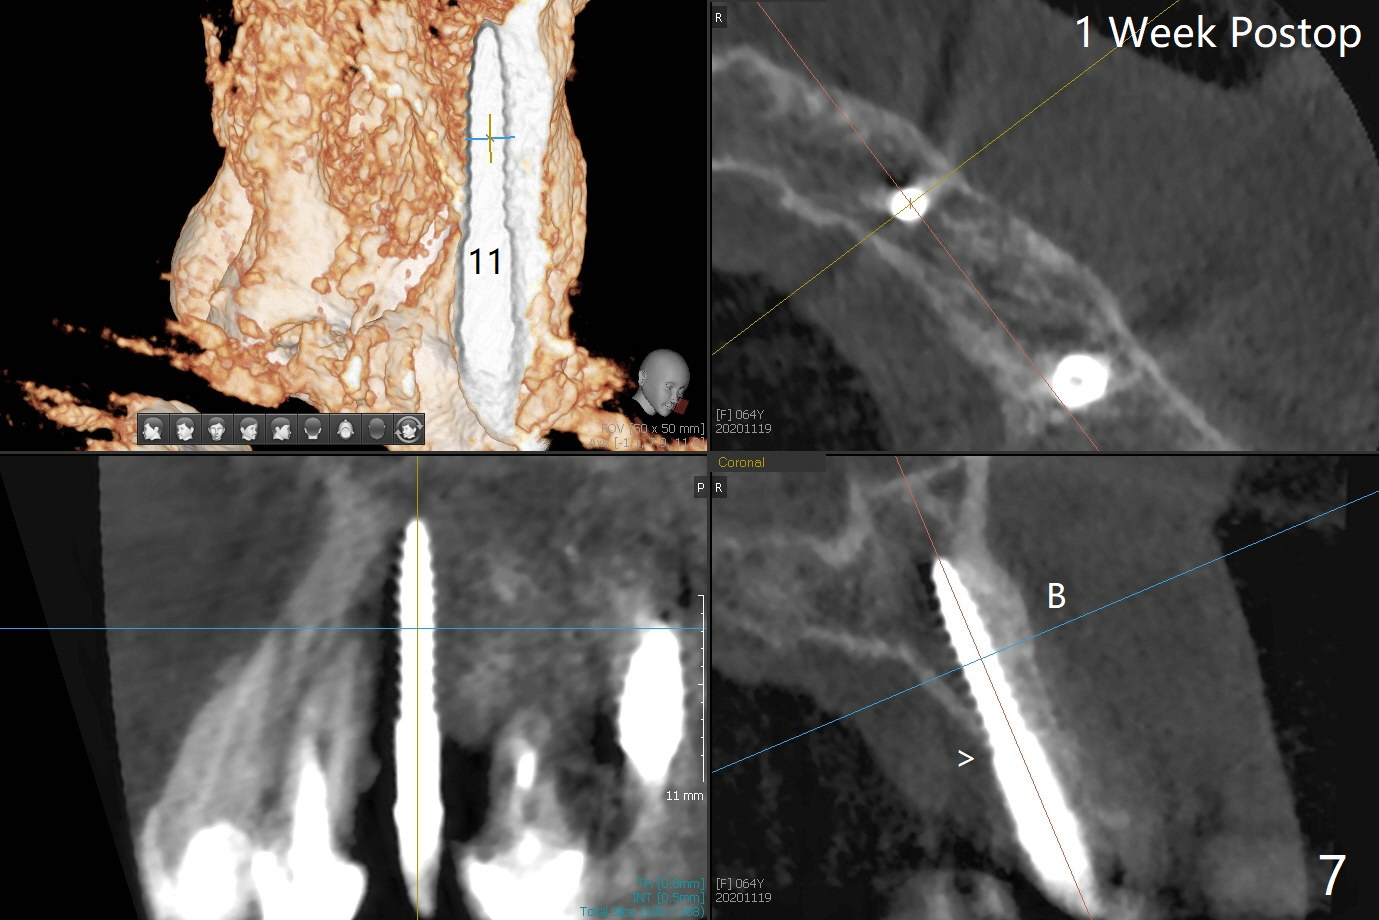

害怕病人局麻药很慢起效,术中身体会动,术中决定减小右下6,7植体直径0.5毫米(与导板设计相比),一旦植体越过牙槽嵴顶骨皮质,稳定性突然减低(图一)。尽管扭力10-15Ncm,为了避免二期手术,放置愈合基台(图二),6基台没有就位(箭头),因为植体种太深了,牙槽骨阻挡(*)基台就位。当取出6基台时,植体一起旋出,重新植入时,就没有种那么深(图三:箭头,与图一,二对比)。由于扭力低,只好放置愈合帽,骨粉(*),GEM Cap(6-9月胶原膜)和牙周胶水。由于导板设计缘故,左上5拔除,种植后,才开始左上3一段式植体植入(图四),5也植入太深(图五),必须放置最小直径最长袖(cuff)的基台(图六),今后导板即刻植牙先不要到达设计深度。术后一周CT显示尖牙植体位于牙槽骨内(图七 (>:腭侧牙槽嵴))。Bone graft fills in the buccal apical defect at #13 one week postop (Fig.8 <). 术后两个月左上3临时牙冠折裂,5松动(图九,十),后者取出衬里,软组织愈合。术后8个月左上3,5取模,右下6 uncover,愈合帽表面覆盖骨质,把7号牙愈合基台放到6号牙上,而7号牙放置4.5x4(4)毫米修复基台,固定牙周敷料,这样6号牙伤口不必缝合。术后8.5个月右下6放置4.5x7.5(4)毫米基台,发现7基台没有就位(图十一:箭头),通过旋转7 基台,终于就位(图十二),螺丝往下移位(与图十一:横线对比),但是基台边缘太低,不利于取模。改用5.5x4(5)毫米UF基台,临床上不能就位,局麻使用5.5毫米Profile Drill后,才能就位(图十三),螺丝下端超越最低螺沟(横线)。